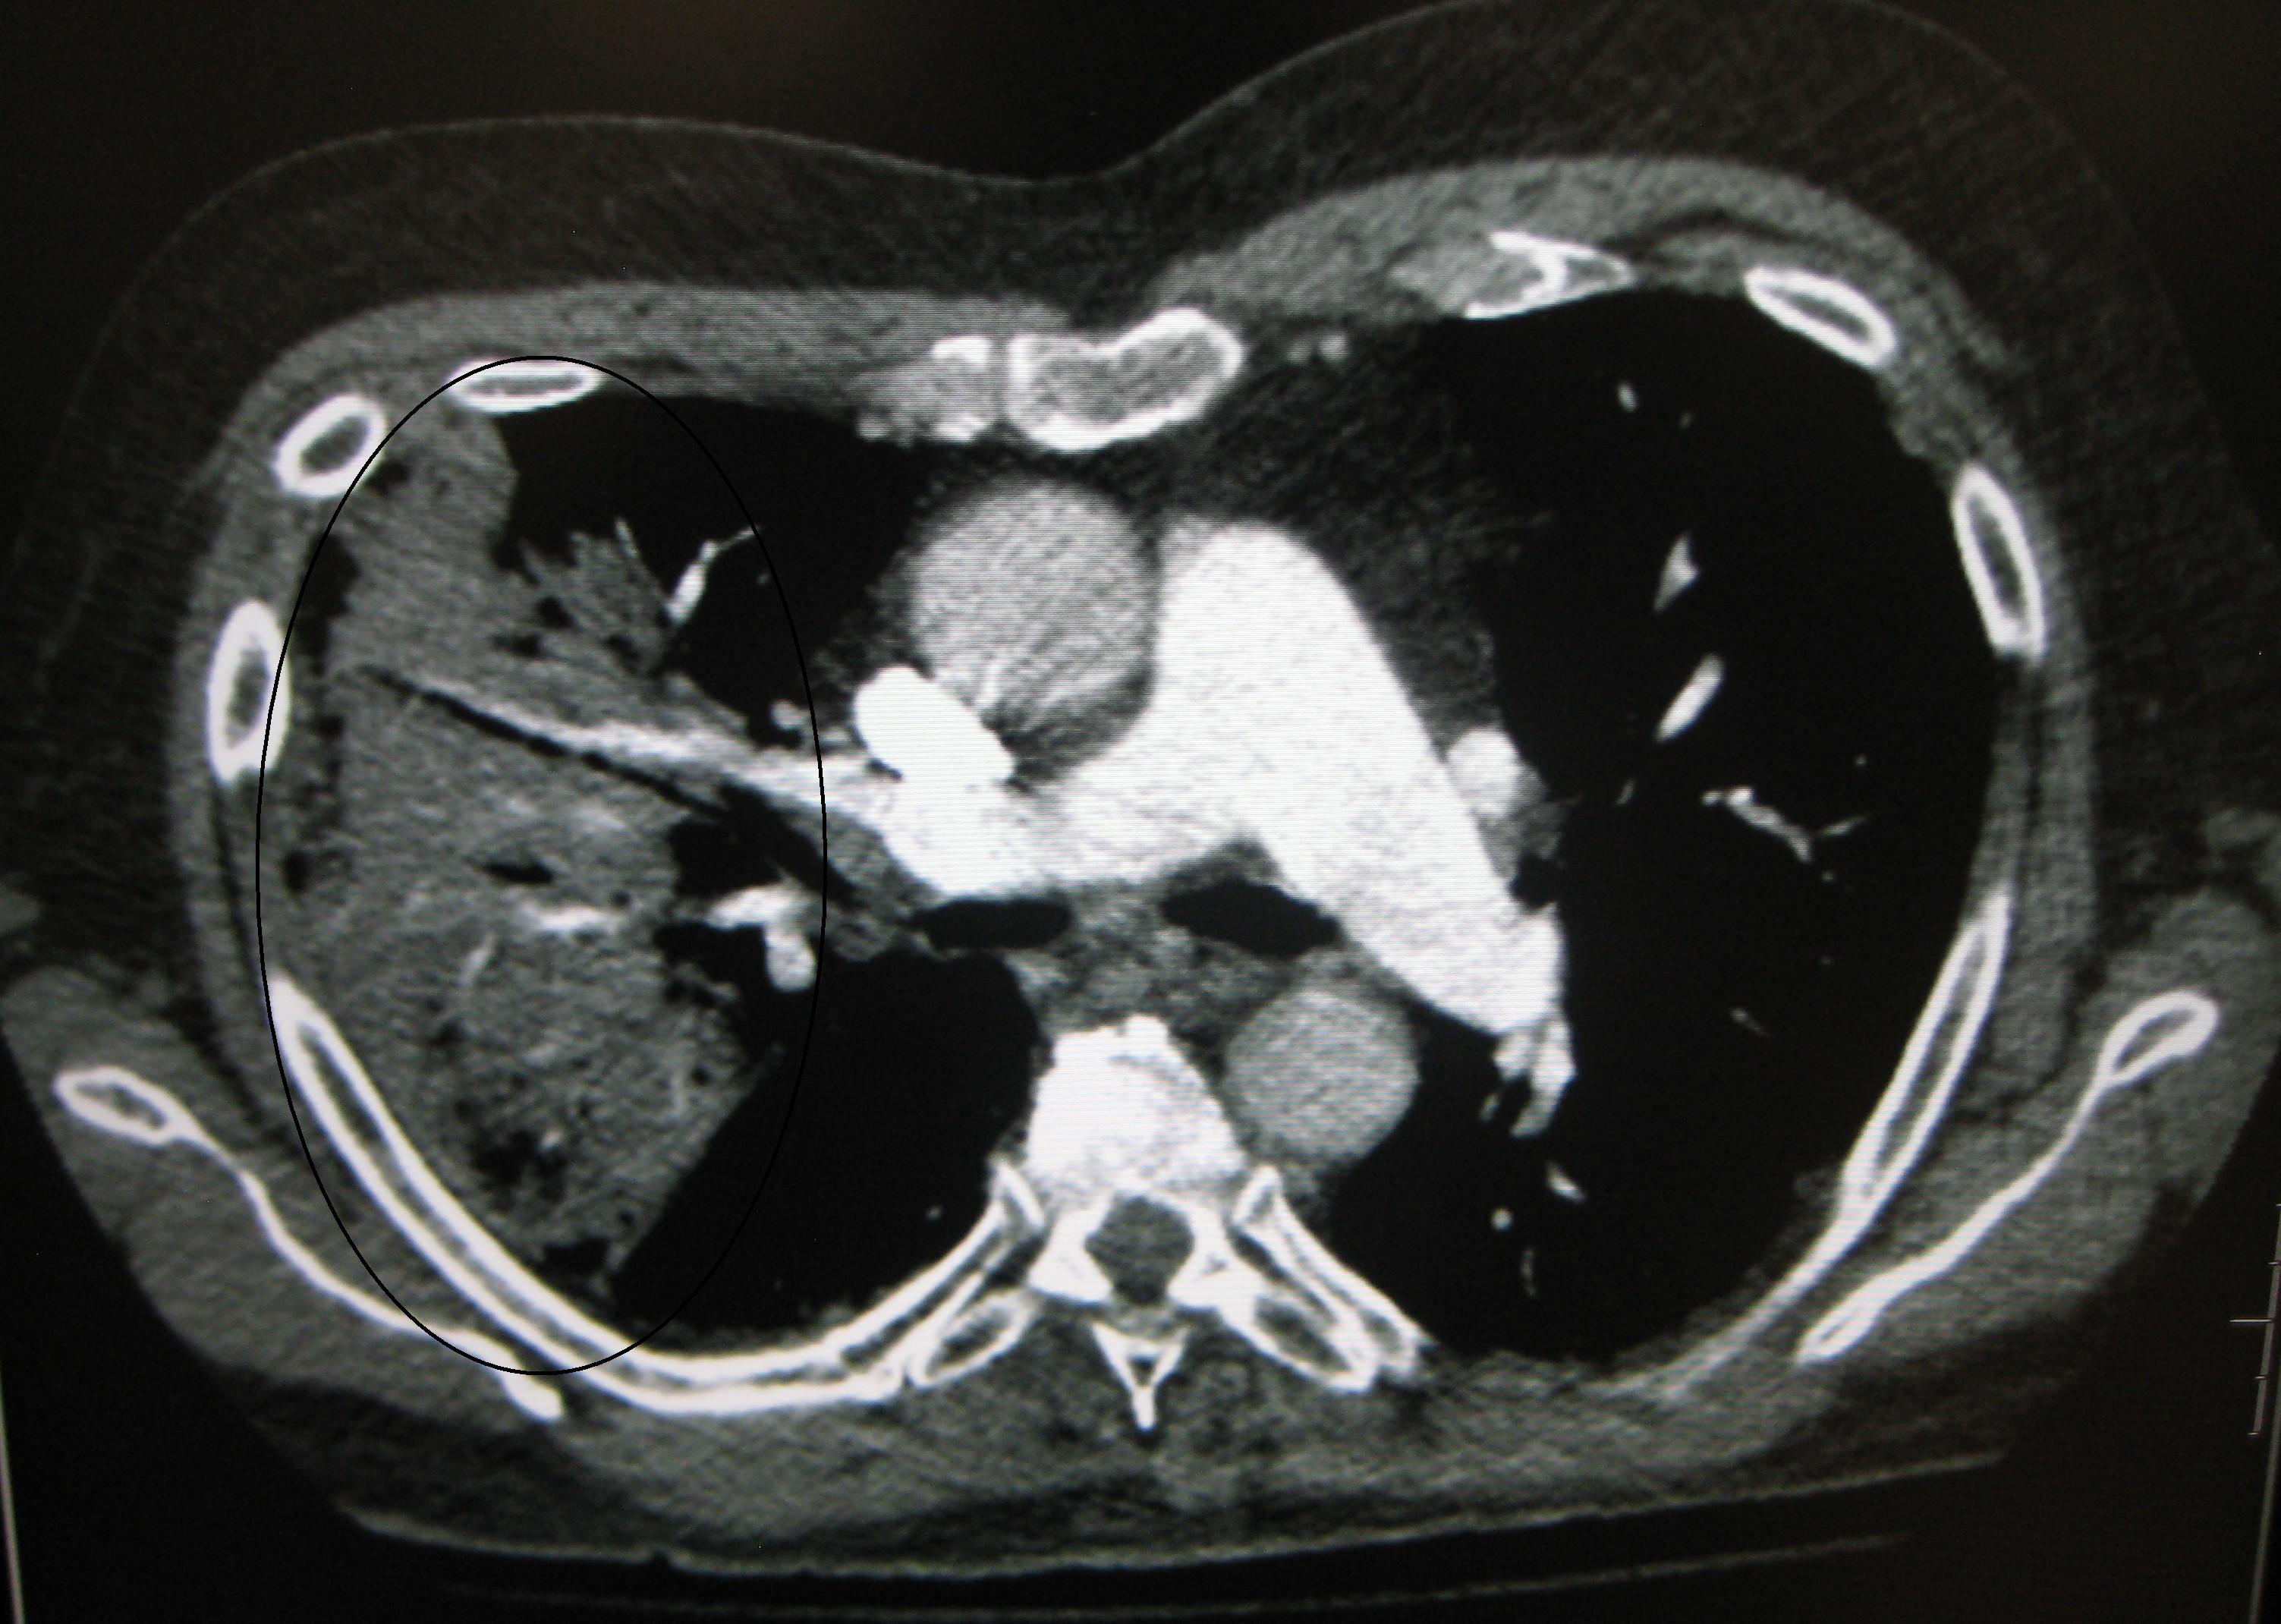

CT 스캔은 불확실한 경우 추가 정보를 제공할 수 있으며,[72] 흉부 방사선 사진이 불분명한 경우(예: 만성 폐쇄성 폐 질환에서 숨겨진 폐렴) 더 자세한 정보를 제공할 수 있다. 치료에 반응하지 않는 사람들의 폐색전증과 진균성 폐렴을 배제하고, 폐농양을 검출하는 데 사용될 수 있다.[78] 그러나 CT 스캔은 비용이 더 비싸고, 방사선량이 더 높으며, 병상 옆에서 시행할 수 없다.[78]

드물게 폐에 세균이 감염된 체액 주머니인 폐농양이 형성될 수 있다.[137] 폐농양은 흉부 X선이나 CT 스캔으로 확인할 수 있으며, 흡인성 폐렴에서 주로 발생한다.[137] 장기간 항생제 치료가 필요하며, 때로는 외과 의사나 중재 방사선과 의사의 배액이 필요할 수 있다.[137]